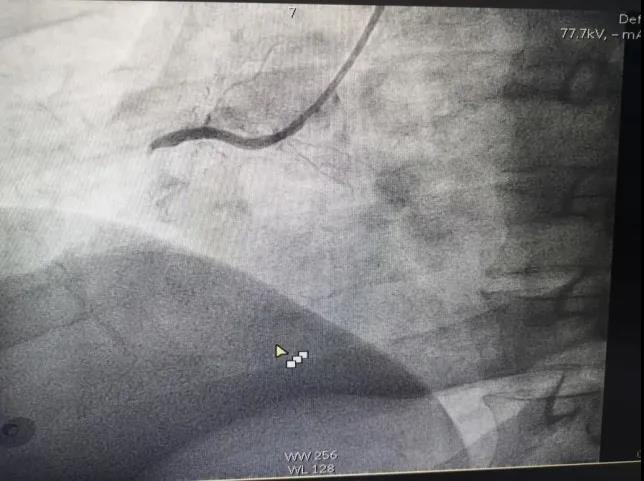

成都市第一人民医院和M老师及其家属配合,实力上演教科书式“真实演练”。在急救过程中,清醒的M老师还亲自指挥抢救,此时却突然心脏骤停,医院急救团队争分夺秒,成功救回心脏骤停20分钟的M老师。 “抢救我的都是我培训过的学生,是他们让我获得重生。”近日,正在康复中的M老师说:“这次是我用生命考核了医院曾经培训过的急救医护人员,证明他们确实是急救技术过硬的团队。” M老师曾担任成都市第一人民医院急诊科主任,目前在成都市120急救中心做急救培训。 3月5日,成都市第一人民医院病房内,M老师回忆了2月27日当天惊心动魄的经历。 当天,他在春熙路的母亲家午休,忽然感到一阵胸痛,15分钟都没缓解,多年专业素养告诉他:“我好像发生心梗了!”他让家人第一时间拨通120急救电话,救护车在7分钟内迅速赶到。 “快,给我拉张心电图。”这是医生进门后M老师对急救医生说的第一句话。查看检查结果后,M老师请医生给自己用了药。上救护车后,“喉咙灼烧难忍,疼痛一直延伸到胃。”M老师被送到成都市第一医院急诊科。 2月27日下午四点半,医院急诊科、心内科、重症医学科医生集体为M老师会诊。 “刚到医院,救护车的医生及时提供了心电图检查结果,为我们诊断提供了重要依据。”心内科医生刘童说,大家争分夺秒给M老师做检查,并准备做手术。M老师虽然躺在病床上,但意识清醒的他还要参与会诊,给自己下诊断,给自己开药方,亲自指挥抢救自己。 “我应该是得了……”M老师正对急救团队成员说自己的情况,话音未落,他忽然眼珠一翻,心电图变成一根直线,呼吸也没了,病情急转直下。 好在危险情况发生在市一医院急诊科,病情演变在医生眼皮下,而且是最佳救命地点。 持续胸外心脏按压,室速室颤电击除颤4次,麻醉科快速气管插管,机械通气及心肺复苏40余分钟……M老师的心跳和呼吸终于稳定了。 “从来没有这么紧张过。”急诊科护士长胥丽事后回忆:“他是我们急诊科老主任,既然心脏骤停在我们急诊科,我们无论如何都要把他救回来。” M老师在昏迷中,在各种仪器设备的强力生命支持条件下,由心血管介入团队对其完成了急诊冠脉造影检查——心脏右侧冠状动脉完全堵塞,伴有大量血栓形成。这是急性心肌梗死,需要马上手术开通血管。 术前,医院的专家团队做好了各种应急准备工作,临时心脏起搏器、主动脉球囊反搏,连心脏外科的ECMO人工膜肺团队也作为B计划处于待命中。 心脏介入手术持续了差不多一个小时,从M老师一根堵塞的血管中抽出了大量新鲜血栓,并在严重狭窄的部位植入了两枚支架,整个血管恢复了良好的血流。 重症医学科的医生在手术中对M老师的生命体征、镇静镇痛以及呼吸支持做出了严密细致的监测和管理,保障了手术的安全性。 手术成功后,M老师也被迅速转入重症医学科接受进一步的监护和治疗。 从抢救,到手术,再到进入ICU,数十位医护人员参与,令人感动。 “这位老前辈,用自己的生命给医生们上了一堂‘含金量’超满溢的急性心梗多科协作急救课。他得救,除了医院的精准高效抢救,还要归功于他自己,以及兄弟医院的专业急救。”心内科医生刘童总结了M老师得救的五大因素: 一是M老师对心梗的自我了解和重视,发病后第一时间向120中心专业医疗团队求救。 二是M老师及时在急救医护人员的严密监护下送达医院急诊科,医生得以目睹完整的发病过程,没有其他非专业因素的干扰,对于及时准确的判断病情,提供了重要依据。 三是M老师选择了有重大危急重症抢救能力的医院,医院拥有专业的生命支持团队和各种先进仪器设备,能够提供最快速有效的抢救措施。 四是M老师抵达市一医院后,跟救护车的医生第一时间提供了“首份”心电图检查资料,这是最为关键最为重要的疾病诊断证据,一医院医生几乎是看了一眼就准确判断出了病灶部位。 五是M老师家人高度配合。抢救过程中,M老师家人对医生完全信任,对任何抢救措施都毫不质疑,马上同意手术,为M老师赢得最佳抢救时间。 这五个因素环环相扣促使抢救成功。M老师及其家人的一系列正确举措,成为医生们交口称赞的教科书式病人。 目前,M老师已经转回普通病房,病情明显缓解,精神状态良好。 M老师的家人提起一个戏剧化的事:“M老师发病后,医院救护车几分钟就到了,提供救护车医院的医护人员说,还以为是M老师在搞急救演练抽查,没想到M老师真的发病了。” M老师也说,这次以这种特殊的方式回到医院,他感到特别亲切,本人及家属都格外感激。“我都离开这么多年了,大家都还是那么熟悉……这次我是在用生命考核曾经培训过的急救医护人员,证明他们是合格的。”来源于成都日报、广州日报,转载目的在于传递更多信息,并不代表本网站赞同其观点和对其真实性负责。如涉及作品内容、版权和其它问题,请在后台联系微信,我们将在第一时间删除内容!